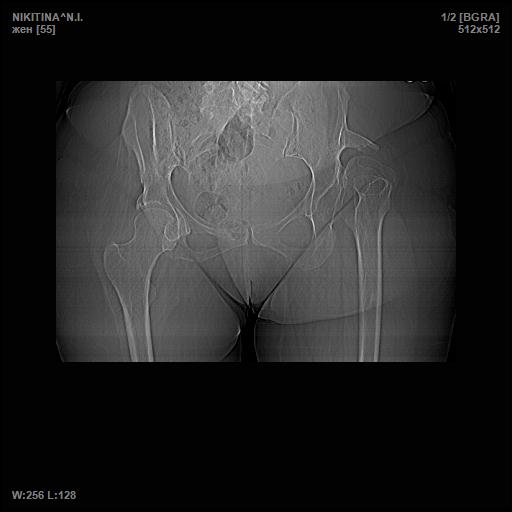

[Ortho] Врожденный вывих бедра

Простите, забыл выложить снимок